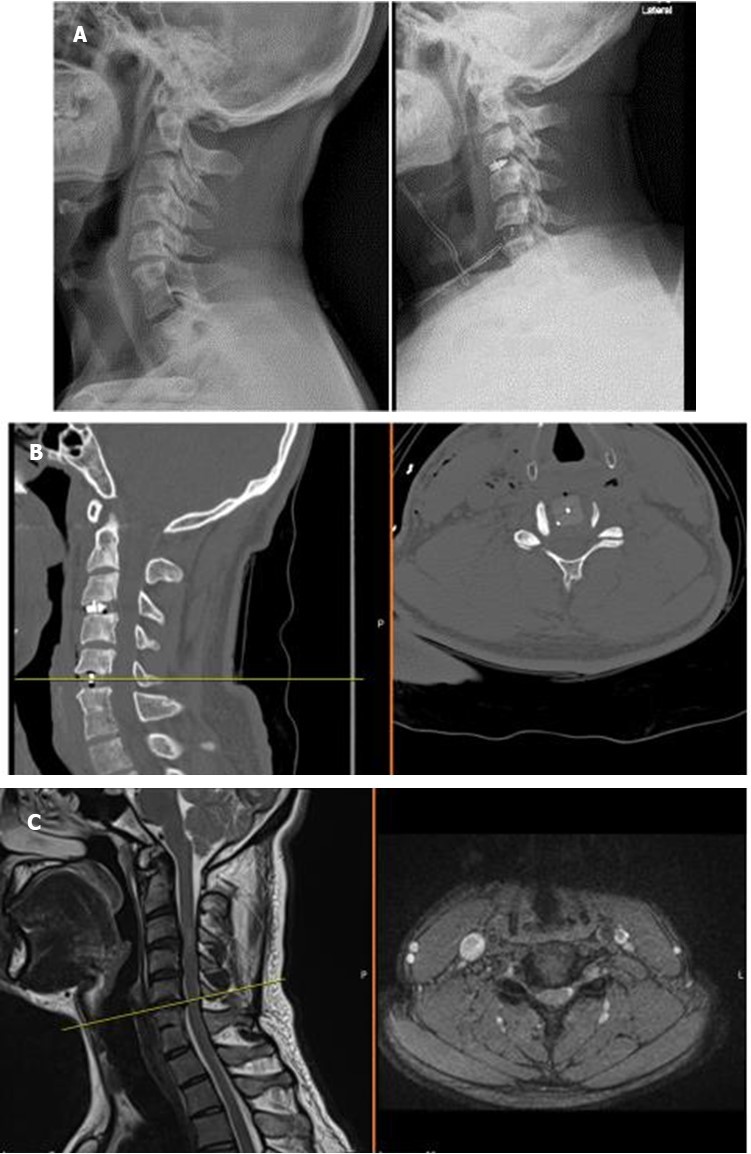

The operative technique was selected concerning our novel “Yilmaz-Yucesoy Classification System” (Table 3). Accordingly, 1 patient (4.54 %) had non-surgical treatment (Yilmaz-Yucesoy Grade 1), 6 patients (27.27 %) received anterior cervical arthroplasty (Yilmaz-Yucesoy Grade 2) (Figure 1), 7 cases (31.81 %) received anterior cervical discectomy or corpectomy and fusion with cervical cage and plate (Yilmaz-Yucesoy Grade 3) (Figure 2). These latter patients did not have cervical spinal instability but had spinal stenosis at more than 1 level. They needed at least 2 level discectomy or corpectomy due to the ossification of posterior longitudinal ligament or osteophyte formation. Eight patients (36.36 %) with cervical spinal instability were performed anterior cervical discectomy or corpectomy and fusion with cervical cage and plate (Yilmaz-Yucesoy Grade 4) (Figure 3).

Figure 1A, B, C.X-ray, computerized tomography, and magnetic resonance imaging views of a Yilmaz-Yucesoy Classification System Grade 2 patient.